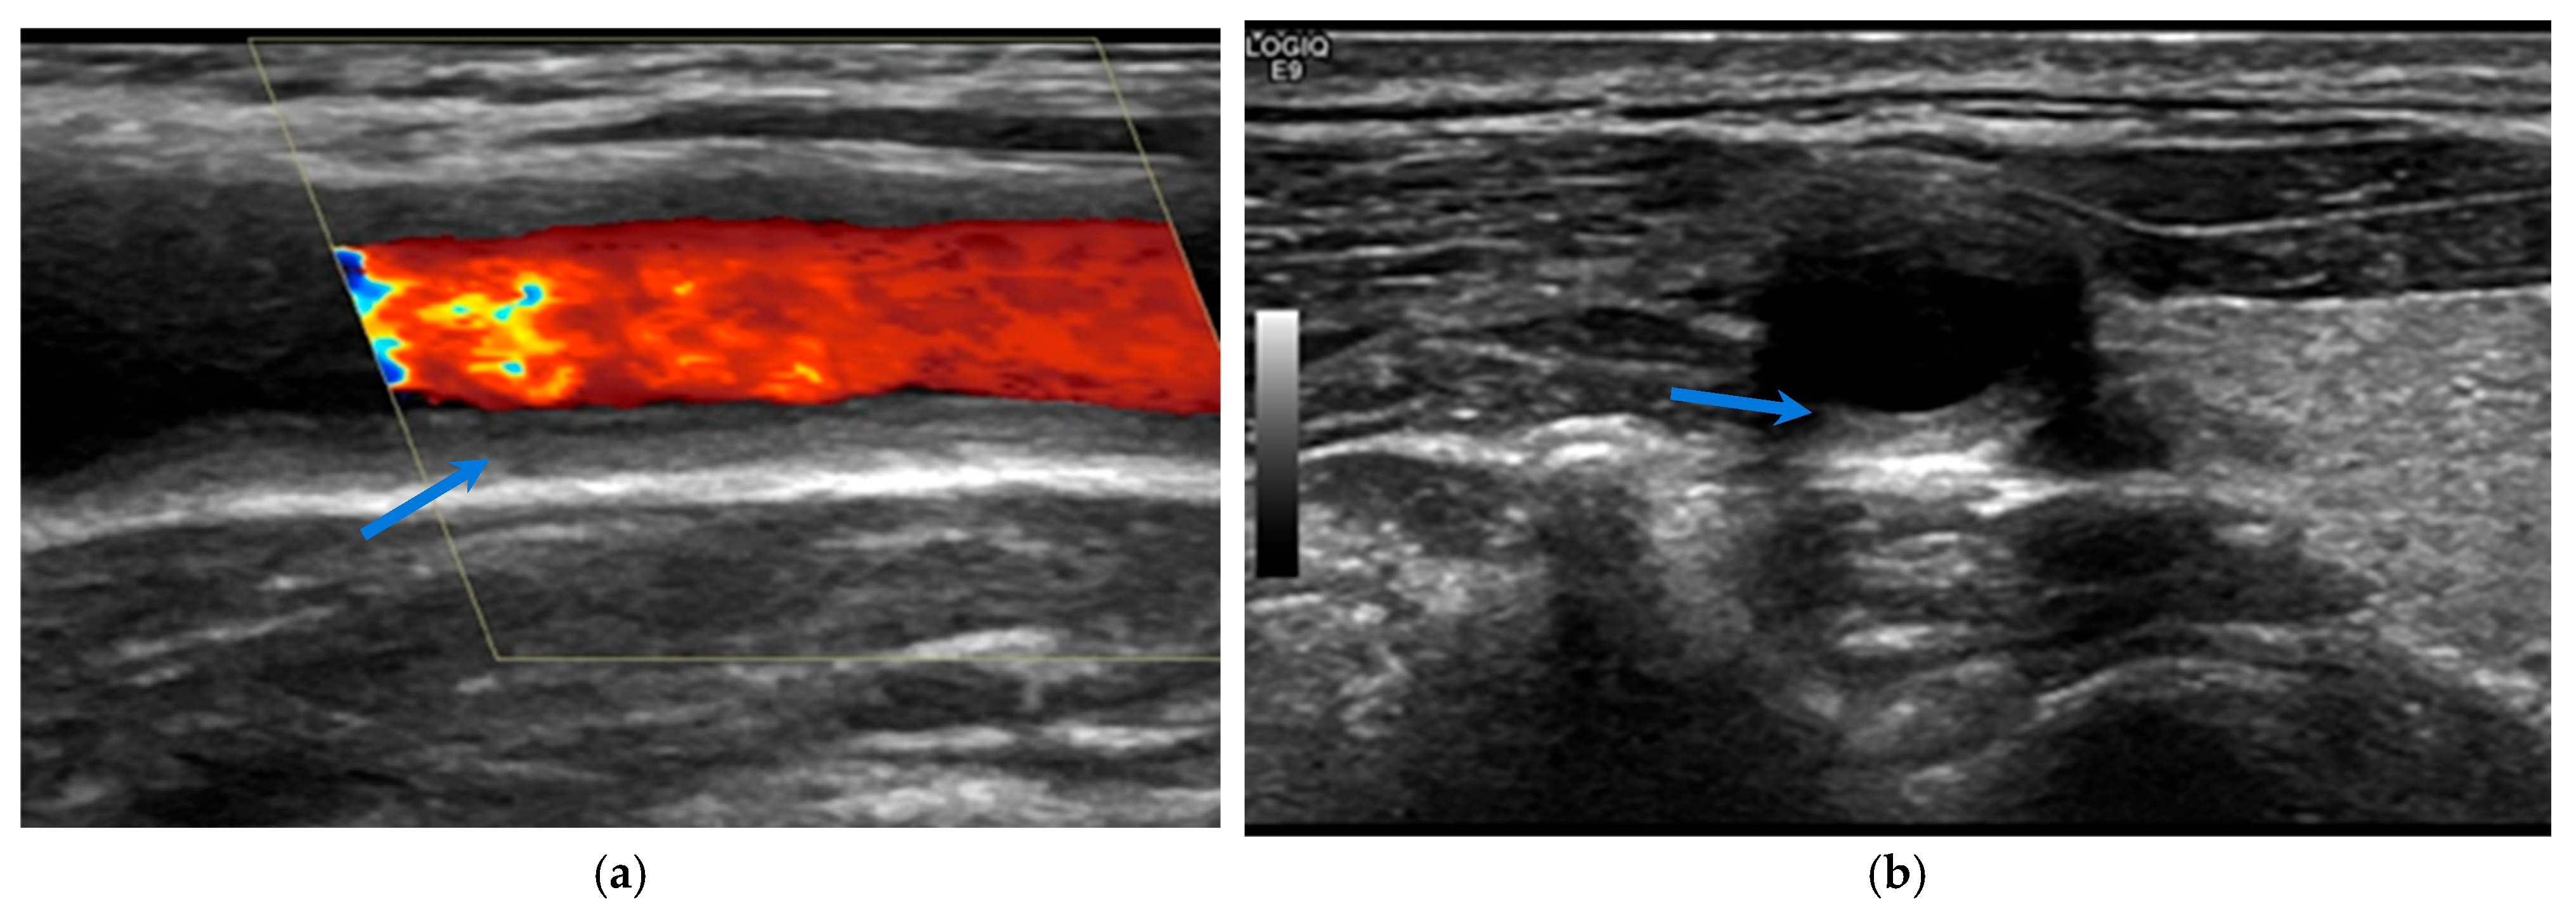

2.2. Takayasu Arteritis

- Ma, L.-Y.; Li, C.-L.; Ma, L.-L.; Cui, X.-M.; Dai, X.-M.; Sun, Y.; Chen, H.-Y.; Huang, B.-J.; Jiang, L.-D. Value of contrast-enhanced ultrasonography of the carotid artery for evaluating disease activity in Takayasu arteritis. Arthritis Res. Ther. 2019, 21, 24. [Google Scholar] [CrossRef] [PubMed]

- Dong, Y.; Wang, Y.; Wang, Y.; Tian, X.; Li, J.; Yang, Y.; Ge, Z.; Zhang, L.; Zou, M.; Wang, H.; et al. Ultrasonography and contrast-enhanced ultrasound for activity assessment in 115 patients with carotid involvement of Takayasu arteritis. Mod. Rheumatol. 2023, 33, 1007–1015. [Google Scholar] [CrossRef] [PubMed]

- Giordana, P.; Baqué-Juston, M.C.; Jeandel, P.Y.; Mondot, L.; Hirlemann, J.; Padovani, B.; Raffaelli, C. Contrast-enhanced ultrasound of carotid artery wall in Takayasu disease: First evidence of application in diagnosis and monitoring of response to treatment. Circulation 2011, 124, 245–247. [Google Scholar] [CrossRef] [PubMed]

- Magnoni, M.; Dagna, L.; Coli, S.; Cianflone, D.; Sabbadini, M.G.; Maseri, A. Assessment of Takayasu arteritis activity by carotid contrast-enhanced ultrasound. Circ. Cardiovasc. Imaging 2011, 4, e1–e2. [Google Scholar] [CrossRef]

- Schinkel, A.F.; Oord, S.C.v.D.; van der Steen, A.F.; van Laar, J.A.; Sijbrands, E.J. Utility of contrast-enhanced ultrasound for the assessment of the carotid artery wall in patients with Takayasu or giant cell arteritis. Eur. Heart J. Cardiovasc. Imaging 2014, 15, 541–546. [Google Scholar] [CrossRef]

- Germanò, G.; Macchioni, P.; Possemato, N.; Boiardi, L.; Nicolini, A.; Casali, M.; Versari, A.; Pipitone, N.; Salvarani, C. Contrast-Enhanced Ultrasound of the Carotid Artery in Patients With Large Vessel Vasculitis: Correlation with Positron Emission Tomography Findings: CEUS of the Carotid Artery in LVV. Arthritis Care Res. 2017, 69, 143–149. [Google Scholar] [CrossRef] [PubMed]

- Wang, Y.; Wang, Y.H.; Tian, X.P.; Wang, H.-Y.; Li, J.; Ge, Z.-T.; Yang, Y.-J.; Cai, S.; Zeng, X.-F.; Li, J.-C. Contrast-enhanced ultrasound for evaluating arteritis activity in Takayasu arteritis patients. Clin. Rheumatol. 2020, 39, 1229–1235. [Google Scholar] [CrossRef] [PubMed]